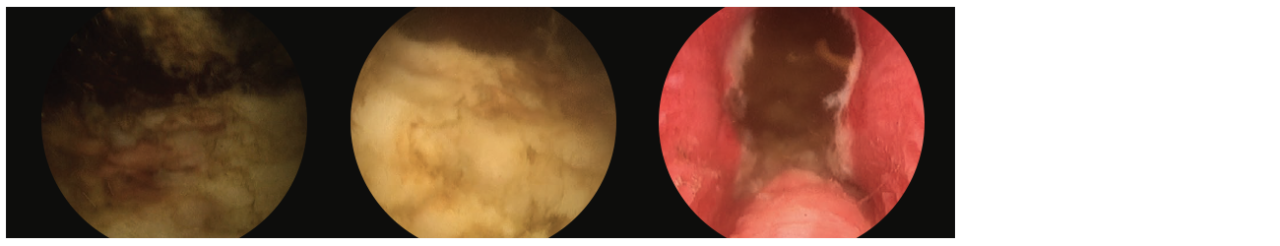

3 scope images. Identifying verumontanum. Figure 3, Part 1: VIT along capsule of floor tissue.

Additional 3 scope images. Identifying verumontanum. Figure 3, Part 2: VIT along capsule of floor tissue.